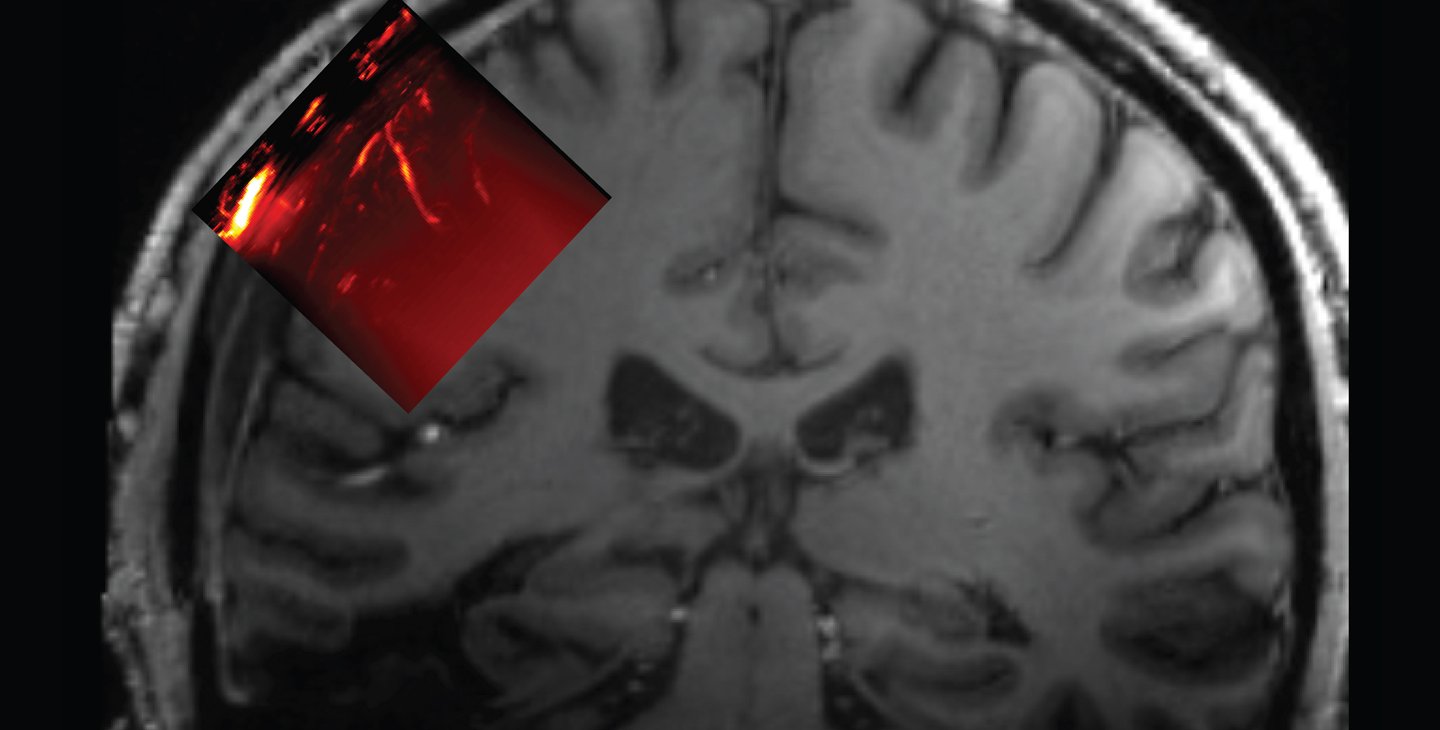

The resulting implant was 4 millimeters thick overall but had a 2 millimeter-thick window through which an ultrasound transducer could image a brain region known as the posterior parietal cortex and, behind it, the motor cortex. "This area of the brain, which is important for forming intentions and carrying out motor actions, has already been thoroughly studied via other methods in our lab," Andersen says. "With ultrasound, we can image the brain up to a resolution of one-fifth of a millimeter."

Schematic showing location of cranial prosthetic and area of brain that can be imaged through this prosthetic.